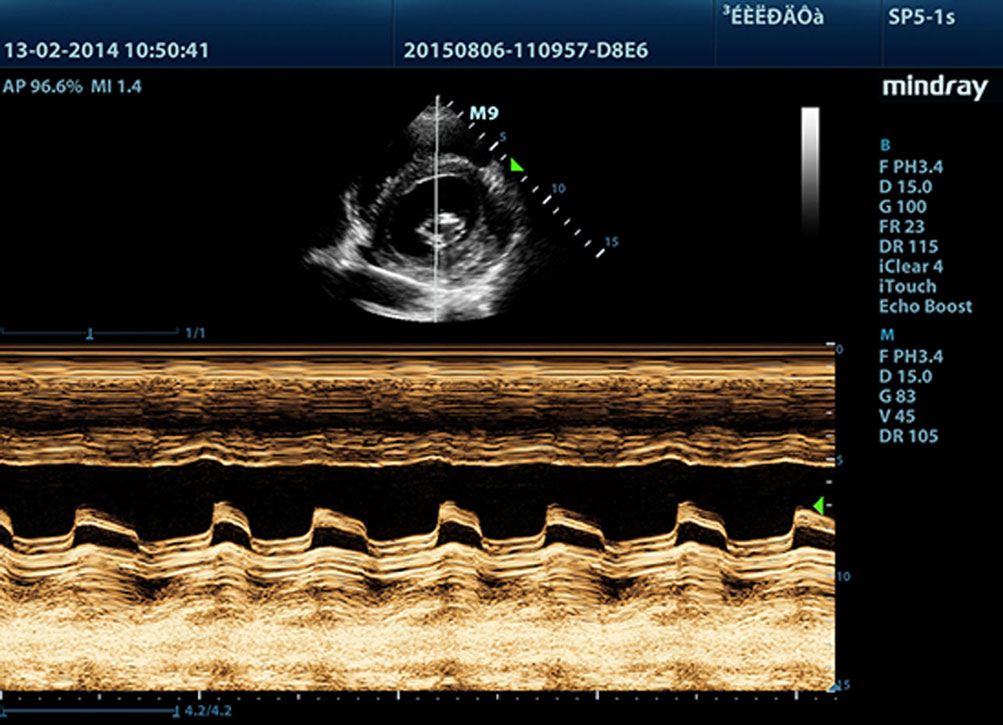

Gratis Xros M?

Precieze anatomische waarneming mogelijk door vrijelijk te plaatsen monsterlijnen onder elke mogelijke hoek. Betere beelden door middel van gelijktijdige weergave van maximaal 3 monsterlijnen.

?

?